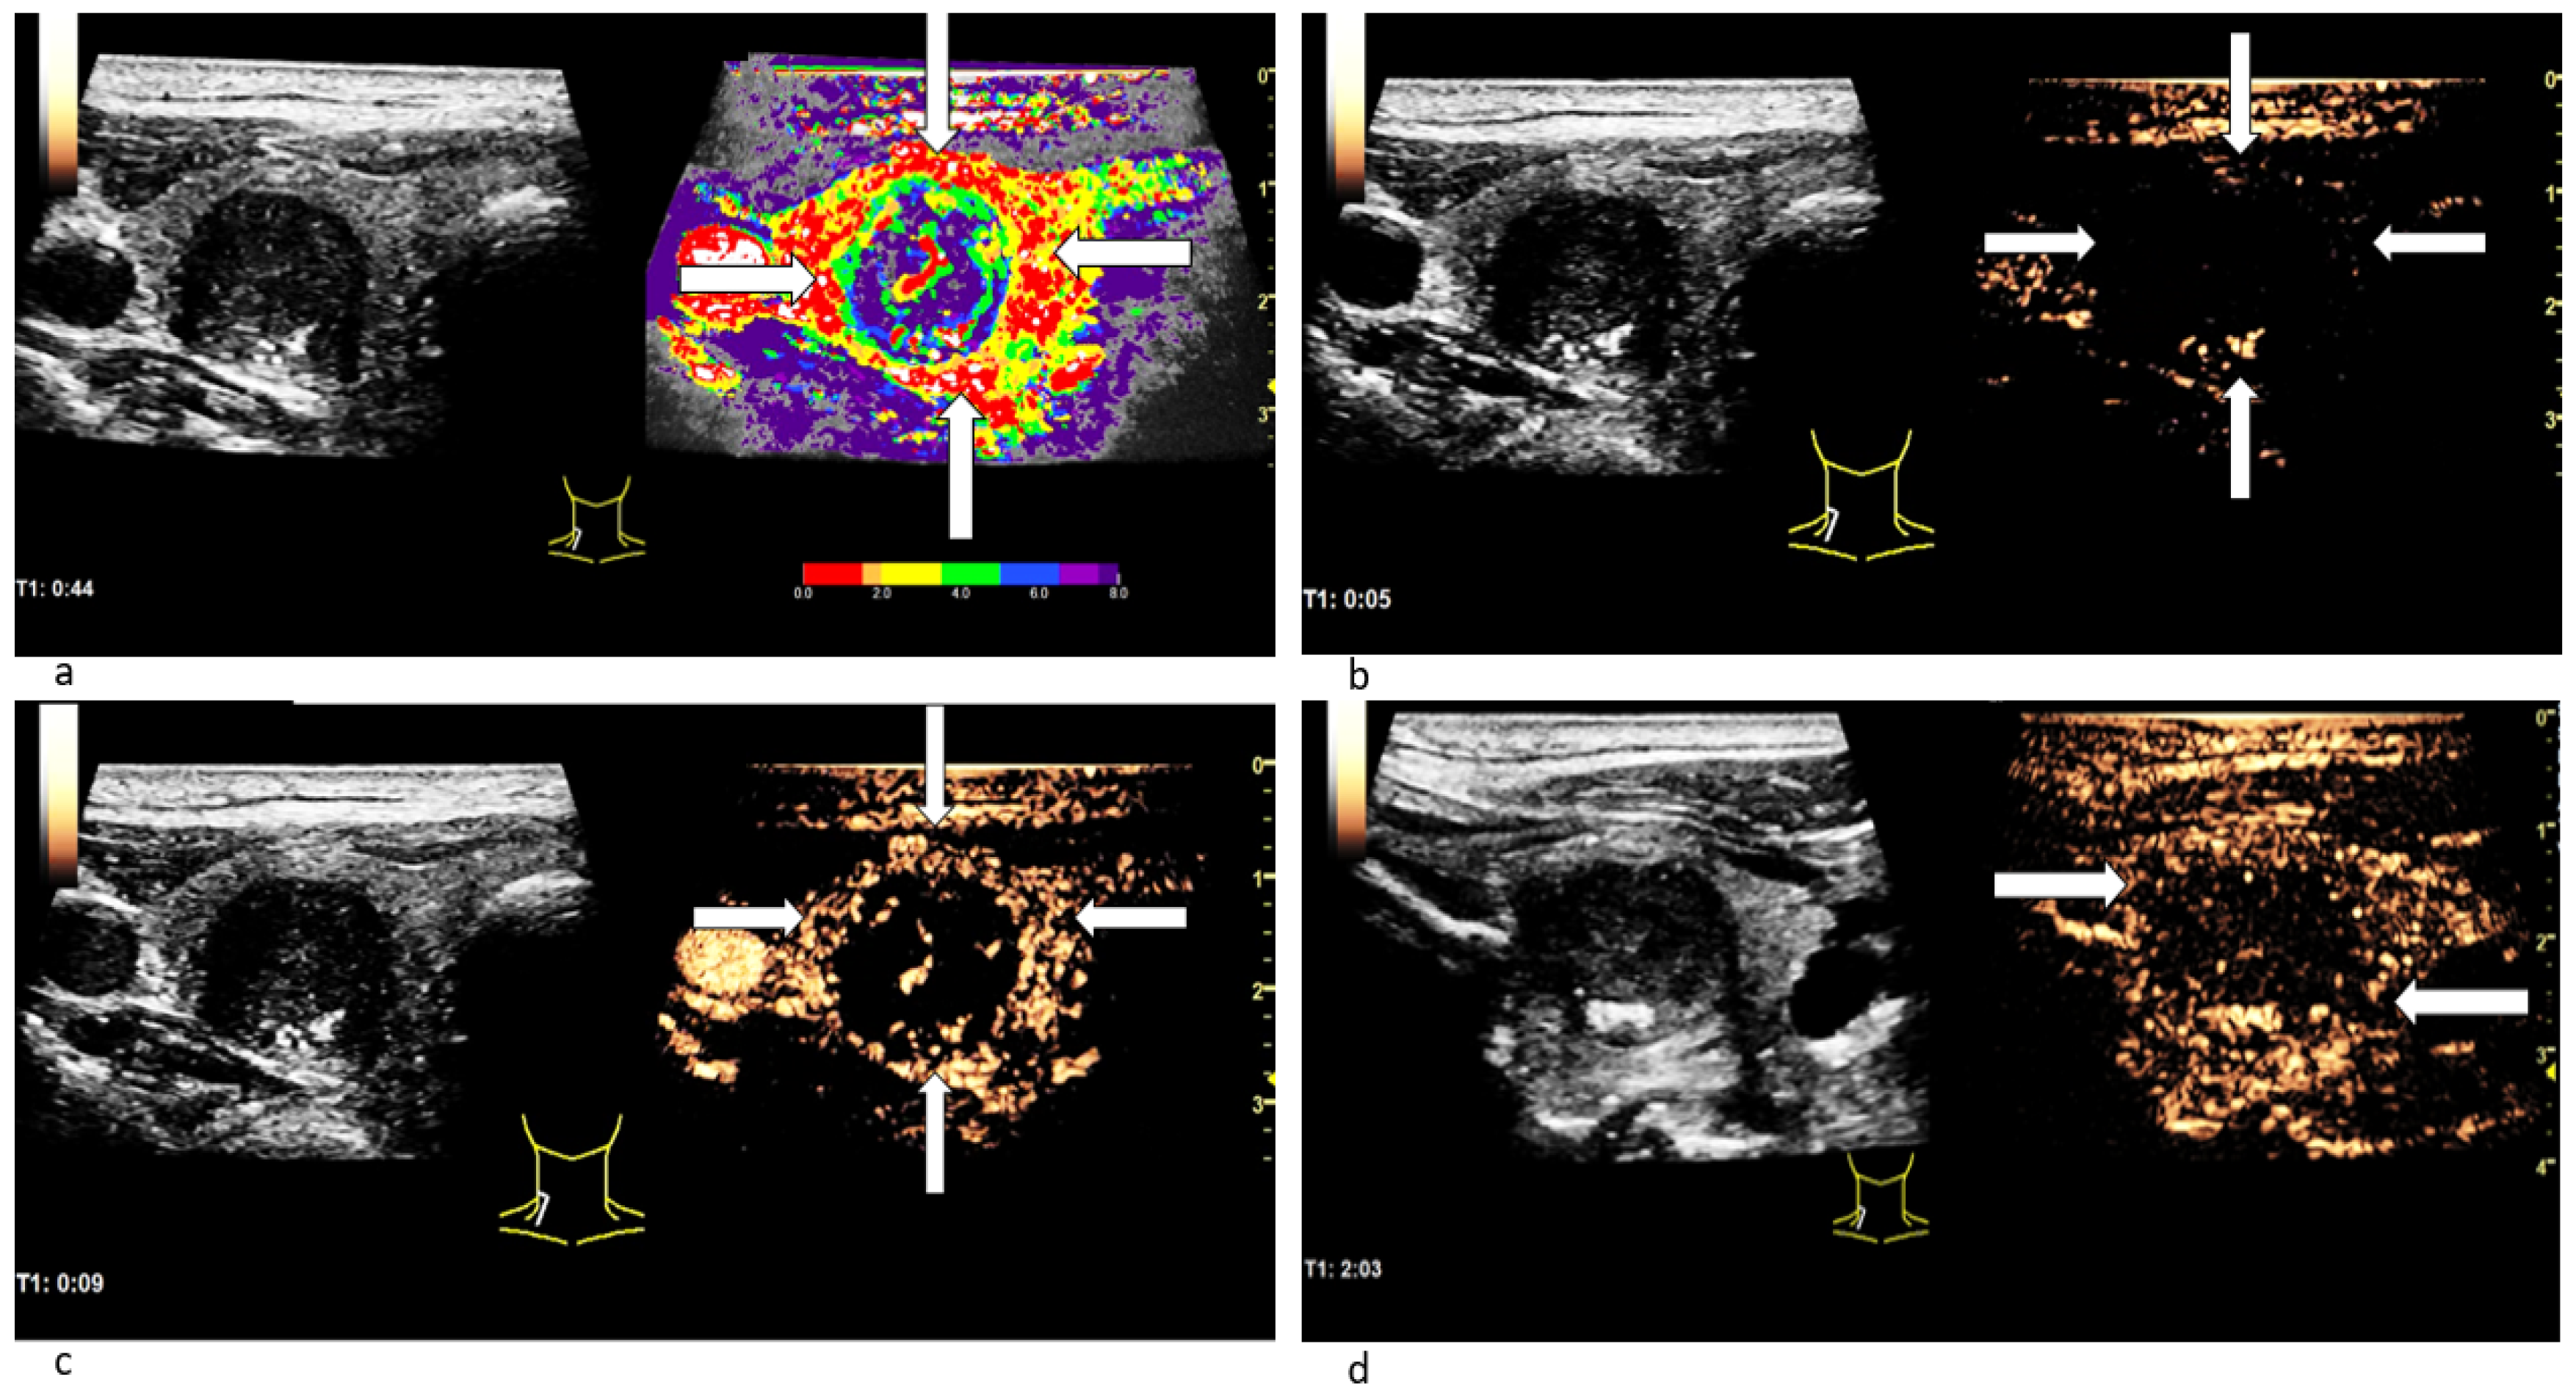

3.3.1. Wash-In Dynamics

3.3.2. (In-)Homogeneous Wash-In and Wash-Out

3.3.3. Time-Intensity-Curve (TIC) Analysis

| CEUS Findings | Benign | Malignant |

|---|---|---|

| inhomogeneous wash-in | 28.4% | 75% |

| partial/complete wash-out | 37.9% | 85% |

| TIC Analysis Mean | Benign (n ± STD) | Benign (%) | Malignant (n ± STD) | Malignant (%) |

|---|---|---|---|---|

| TTP [s] center | 19.7 ± 10.8 | 91.0% | 13.2 ± 6.5 | 89.0% |

| TTP [s] margin | 19.9 ± 8.7 | 91.8% | 13.9 ± 6.5 | 93.7% |

| TTP [s] surrounding tissue | 21.7 ± 15.1 | 100.0% | 14.8 ± 7.6 | 100.0% |

| CEUS | fast marginal wash-in | 88.7 | 21.3 | 50.0 | 96.9 |

| fast central wash-in | 82.6 | 0.9 | 20.0 | 96.8 | |

| inhomogeneous wash-in | 82.6 | 7.2 | 34.9 | 93.1 | |

| partial/complete wash-out | 82.6 | 3.4 | 66.7 | 95.2 | |

| CEUS: TIC | marginal TTP cut-off: 13.1 s | 78.5 | 1.1 | 57.9 | 81.1 |

| central TTP cut-off: 13.5 s | 78.5 | 1.1 | 78.9 | 73.0 | |